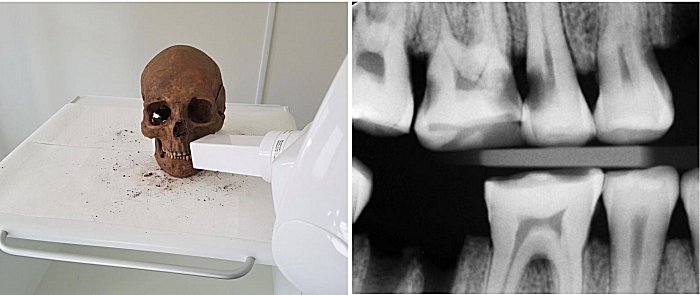

The research team from the University of Gothenburg’s Institute of Odontology worked with an osteologist from Västergötland’s Museum. The skulls and teeth were transported to Gothenburg, where all the examinations were carried out.

The teeth underwent clinical examinations using standard dentistry tools under bright light. A number of X-ray examinations were also performed using the same technique used in dentistry, where the patient bites down on a small square imaging plate in the mouth.